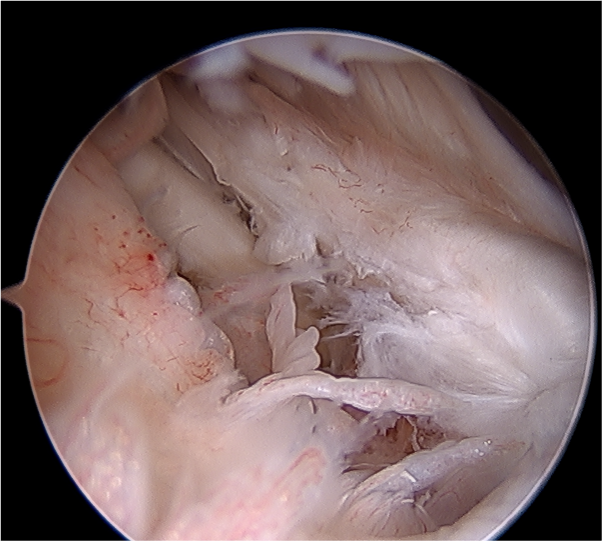

Arthroscopy

Capsule tear anteriorly, extending up into humeral insertion

Side to side repair of capsular tear

Intact anterior labrum with capsular tear, axillary nerve seen below capsular tear in axillary recess